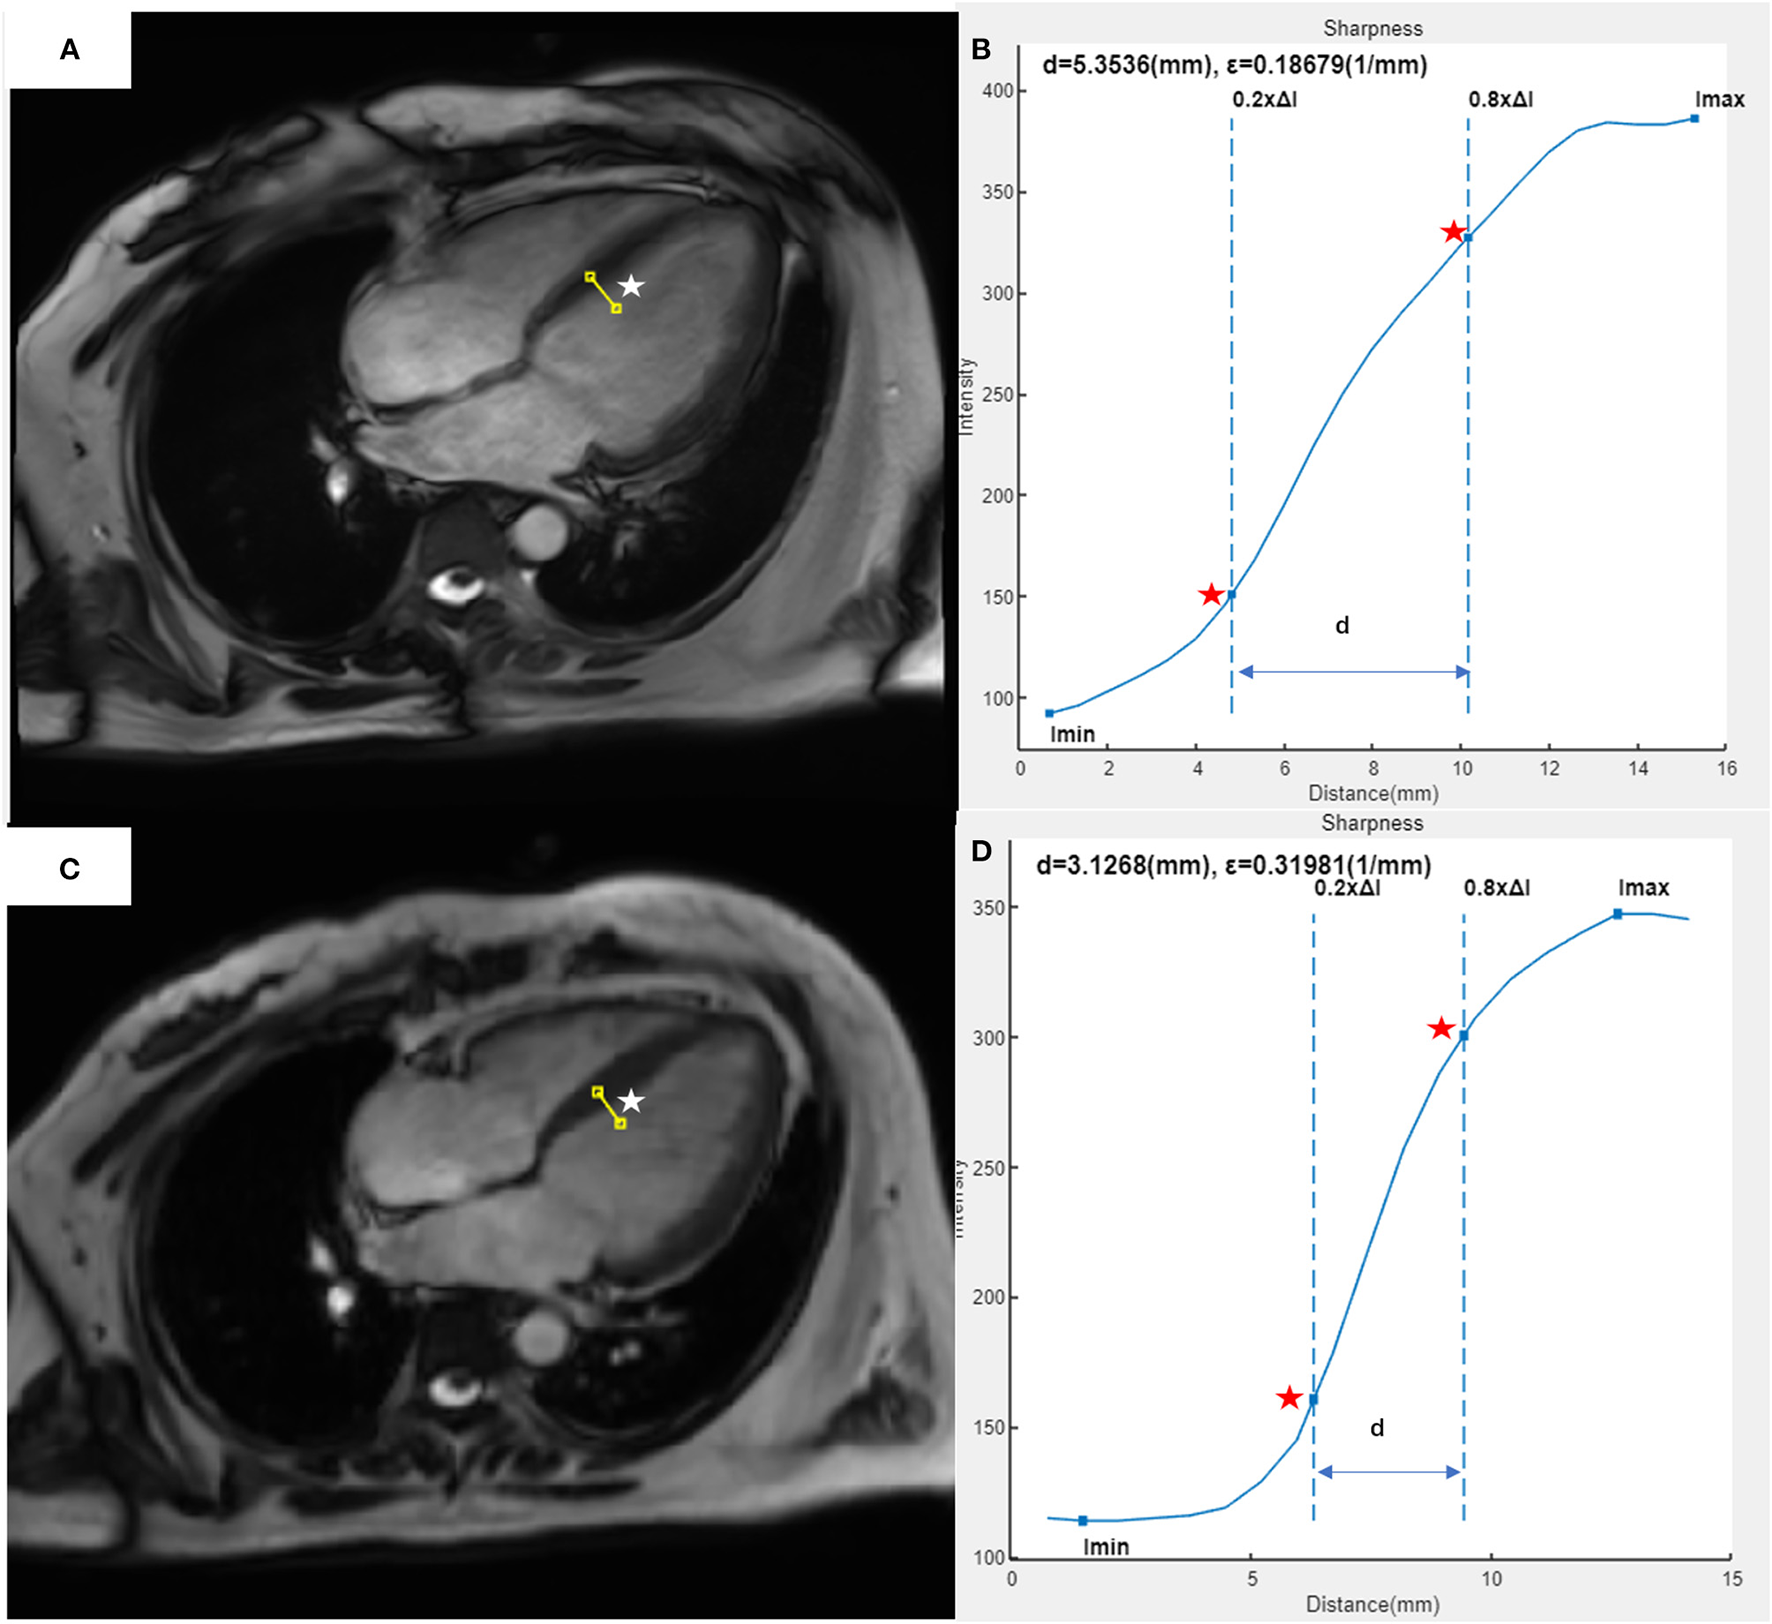

The edge sharpness (ε, expressed in mm−1) was defined as the inverse of the distance (mm) between the positions corresponding to 20% and 80% of the difference between the maximum and minimum signal intensities along the line drawn perpendicularly to the mid-cavity interventricular septum border with the LV blood pool on the end-diastole four-chamber view (17). This assessment was performed using a homemade script in MATLAB (version R2021a; The MathWorks, Natick, MA, USA) (Figure 1).

Figure 1

Example of edge sharpness assessment for a 37-year-old female patient with heart failure and atrial fibrillation, as performed in our study. The image of the 4CH view at end-diastole was acquired with segmented (A) or CSRT (C) bSSFP cine sequence. A line (white star) was drawn perpendicularly to the mid-cavity interventricular septum border with the left ventricular blood pool on each image. In the intensity profile (blue curve) of each line from the segmented cine (B) or CSRT cine (D), the edge sharpness (ε, expressed in mm−1) was calculated as the inverse of the distance [(D), expressed in mm] between the positions (red stars) corresponding to 20% and 80% of the difference between the maximum and minimum signal intensities along the line. 4CH, four-chamber; CSRT, compressed sensing real-time; bSSFP, balanced Steady-State-Free-Precession.